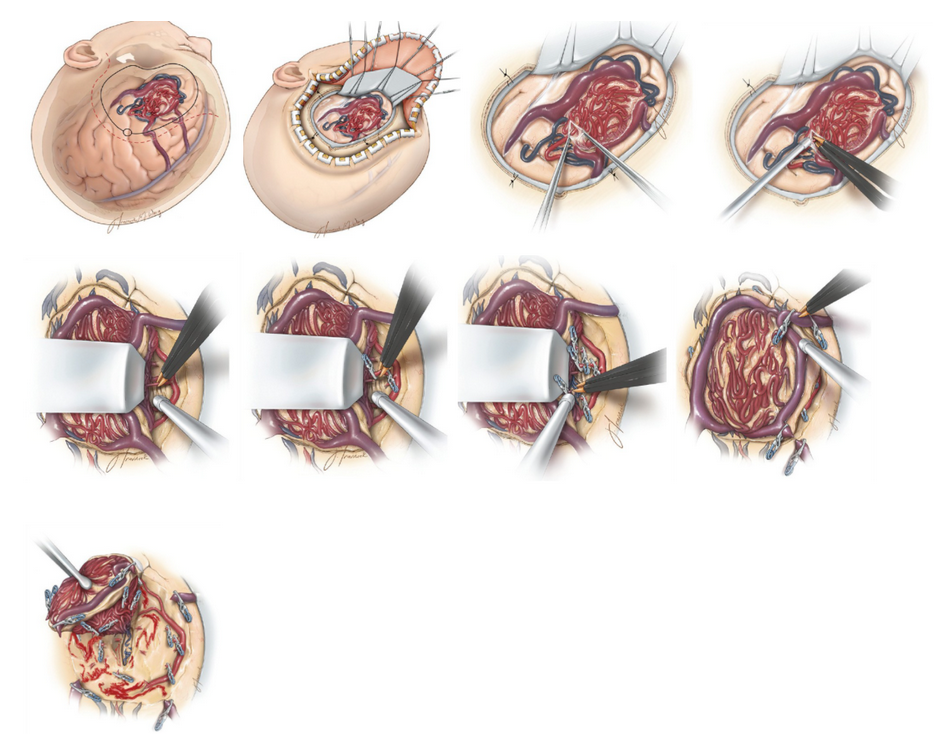

Microsurgical resection is often the best option for AVMs located in favorable areas of the brain because it allows for the immediate and complete cure of the AVM, with a good safety profile. For this treatment, the patient undergoes traditional surgery in the operating room and an angiogram during surgery may be used to confirm that the AVM is removed completely (Figure 5).

Figure 5. Microsurgical Resection of an AVM. a) Incision and craniotomy for generous exposure of a left frontal AVM. b) Intradural view of a left-sided frontal convexity AVM. c) Arachnoid membranes covering the AVM are often thickened and should be generously dissected open to allow for clear identification of margins of the AVM’s free surface and surrounding vessels. d) A surface arterial feeder is identified and occluded using bipolar electrocautery. e) A length of the artery is dissected out and some of the more superficial ones may be occluded with bipolar coagulation. f) Deep arterial feeders may be clipped and divided as they do not easily occlude with bipolar coagulation. g) Parenchymal dissection and division of deep arterial feeders proceed toward the ventricle. h) After all arterial feeders are occluded, the primary draining vein is clipped, coagulated, and transected. i) The AVM is removed from the resection cavity, which is inspected for any persistent bleeding.